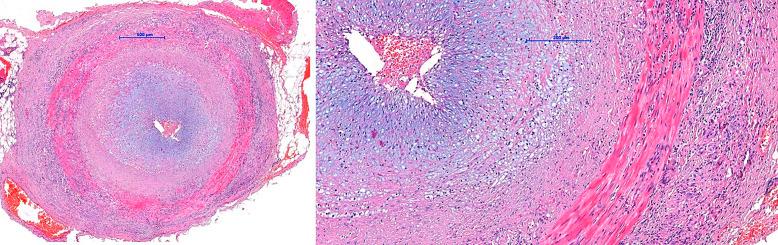

We describe a case of rare irAEs manifested as giant cell temporal arteritis (GCA) followed by severe encephalopathy occurring after continuing immunotherapy in a 66-year-old man with mRCC receiving a combination of ipilimumab and nivolumab in the first line of systemic therapy. GCA occurred 4 months after the initiation of IO and responded promptly to the low-dose prednisone therapy. Four months after the continuation of nivolumab maintenance, the patient was hospitalized due to severe irAE encephalopathy which presented as psycho-behavioral abnormalities and progressive cognitive decline. He was treated with high-dose methylprednisolone which led to complete resolution of the symptoms and IO was permanently discontinued. The patient achieved a durable partial response.

我们描述了一例罕见的irAE病例,表现为巨细胞颞动脉炎(GCA),随后在一名66岁的mRCC男性患者中,在一线全身治疗中接受伊匹木单抗和纳武单抗联合治疗后继续免疫治疗时发生了严重脑病。GCA在IO治疗开始后4个月出现,对低剂量泼尼松治疗迅速产生反应。在继续使用纳武单抗维持治疗4个月后,患者因严重的irAE脑病住院,表现为心理行为异常和进行性认知下降。他接受了大剂量甲泼尼龙治疗,症状完全缓解,IO治疗永久停药。患者获得了持久的部分缓解。